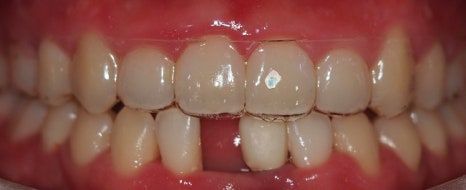

▲최종 구강 사진

이렇게 최종적으로 치료 소요 기간은 8개월 정도 소요되었습니다.

환자분의 협조도 같이 이루어졌기에 치료가 잘 마무리 될 수 있었습니다.